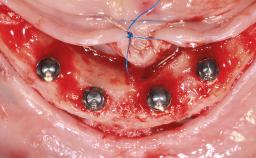

A 65-year-old female patient was referred to our clinic by another patient for evaluation and treatment of her compromised dental clinical situation. The patient presented with a pessimistic attitude and declared she had no confidence in the possibility of improving her oral situation. Her main complaint was discomfort, inability to chew, and collapse of the facial tissues related to her medical history. The patient had a serious domestic accident 18 months before the consultation and suffered from a head injury, followed by 4 months in a coma. She then gradually progressed toward almost complete neurological recovery, although, at the time of the consultation, she still had difficulty walking. The patient suffered a mandibular fracture in that accident, but because her life had been in danger, the fracture had been ignored. Since the patient was immobilized at the hospital for 4 months, the mandibular fracture had healed spontaneously, but the fragments reossified in an incorrect position, which resulted in a complete discrepancy between the positions of the remaining mandibular teeth and the maxillary teeth